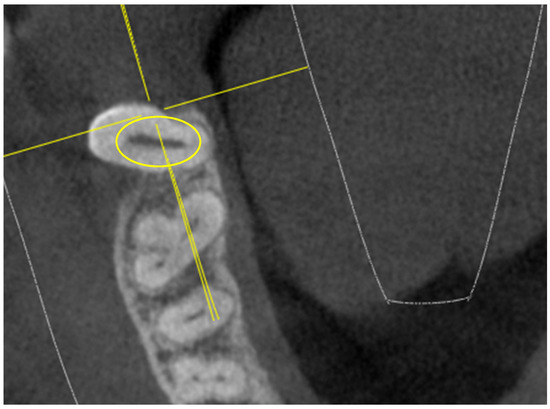

- diameter of root canal orifices;

- distance between intra- and inter-root canals;

| Mb2 diameter | 0.38 | 0.12 (6 NO) | 0.3 | 0.8 (10 NO) | 0.39 | 0.9 (3 NO) | 0.34 | 0.8 (15 NO) | ||

| MB1-MB2 distance | 1.54 | 0.21 | 1.67 | 0.21 | 1.63 | 0.19 | 1.45 | 0.22 | ||

| MB2 diameter | 0.42 | 0.6 (2 NO) | 0.47 | 0.5 (7 NO) | 0.47 | 0.7 (3 NO) | 0.42 | 0.4 (11 NO) | ||

| MB1-MB2 distance | 1.98 | 0.62 | 1.52 | 0.44 | 1.9 | 0.4 | 1.32 | 0.42 | ||